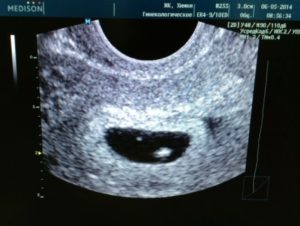

Плодное яйцо – овальное или круглое тело диаметром в несколько миллиметров. Диаметр плодного яйца замеряется во время первого же УЗИ. Учитывая его размеры, специалист может установить срок беременности. Но в некоторых случаях погрешность в определении составляет 1-1,5 недели. Поэтому врач, пытаясь установить срок, учитывает также показатели копчико-теменного размера.

плодное яйцо выглядит как образование в виде шара или овала. Уже в 5-6 недель желточный мешок, который обеспечивает питание эмбриона и выполняет кроветворную функцию на ранних стадиях развития эмбриона, похож на пузырек внутри полости плодного яйца.

Размер плодного яйца на этой стадии беременности составляет от 1,5 до 2,5 сантиметров. Рассмотреть зародыш в это время уже можно. Он выглядит, как пятимиллиметровая полоска, расположенная рядом с желточным мешком. И хотя определить, где у зародыша какая структура и часть пока невозможно, сердцебиение уже регистрируется.

В это время сердечко крохи бьется с частотой 150-230 ударов в минуту.

К концу 7-й недели зародыш уже приобретает свою характерную форму в виде буквы С. В это время он уже открепился от поверхности плодного яйца. На УЗИ уже можно различить голову, туловище и крохотные зачатки ручек и ножек. В плодном яйце просматривается уже сформированная пуповина.